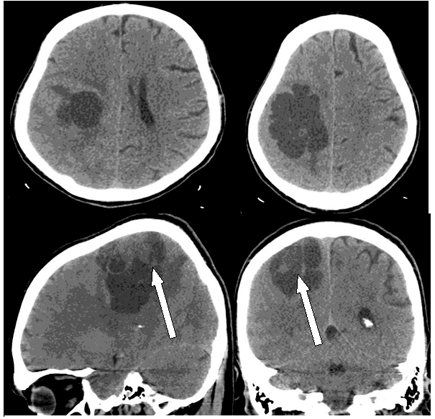

New research published in Neuro-Oncology examines the controversial link between intracranial volume and high-grade glioma.

Patients with resected brain metastases who underwent stereotactic radiosurgery had lower rates of local recurrence compared with observation alone, according to the results of a phase III trial.